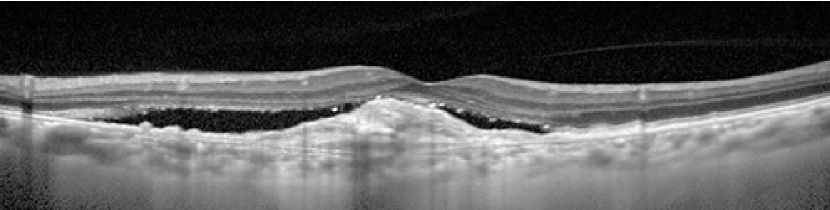

Figure 1: Examples of SD-OCT images: a) dry AMD, b) wet AMD, c) DME and d) normal B-scans.

One of the persistent diseases of the retina is Age-related Macular Degeneration (AMD) which can result in loss of central vision. AMD affects the macula which is an area consist of light-sensitive cells and is responsible for providing sharp central vision. It is estimated that more than 250000 adults suffer blindness due to AMD in United Kingdom [1]. AMD is the term applied to changes in the eye which can be identified by pigmentary abnormalities and considerable drusen, in people aged over 50 years. Drusens are accumulations of lipid material below the retinal pigment epithelium (RPE) and within the Bruch’s membrane, appearing as yellow spots on the retina. AMD disease categorize into two main types: dry form and wet form. Dry form which involves 90% of people with AMD, is a condition in that layers of the macula (including the RPE and the photoreceptors) get progressively thinner. This is called atrophy. The symptoms of the early stage of dry AMD is a change in the pigment or color of the macula plus appearance of tiny drusen on the retina. Existence of Drusen can lead to deterioration and atrophy of the retina. Exuding is the leakage of fluids from blood vessels and when dry AMD does not involve them, it is also called non-exudative AMD. In contrast to dry AMD, there is another kind of AMD where the growth of new weak blood vessels behind the retina can cause serious problems. This situation which is called wet AMD is accompanied by leakage of fluid, lipids and blood from newly grown vessels which can cause scar tissue to form and retinal cells to stop functioning (see Fig. 1). Wet AMD is also exudative AMD due to involving exudation or fluid and blood leakage from new blood vessels [2].

Diabetic Macular Edema (DME), is another retinal disease which is characterized by the accumulation of exudative fluid in the macula. DME is the most prevalent form of sight-impendent retinopathy in people with diabetes [3]. The breakdown of the inner blood-retinal barrier is one of the reasons for this problem (see Fig. 1). Early detection of retinal abnormalities is considerably important in preventing DME and subsequent loss of vision problem [4]. 6% of diabetic people are affected by DME which can resulted in more than 20 million cases worldwide [3].